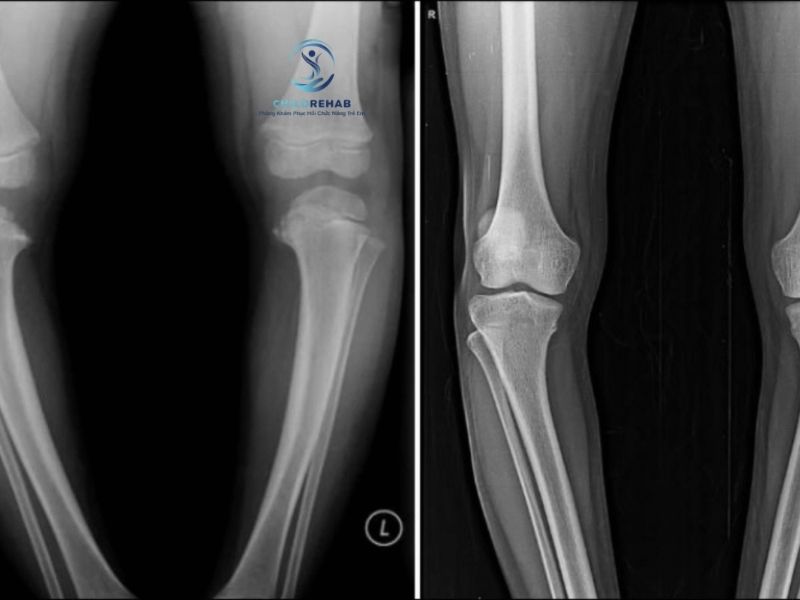

Ngược lại, trong một số trường hợp nghi ngờ bất thường, việc chụp X-quang có thể được sử dụng để hỗ trợ đánh giá cấu trúc xương, xác định nguyên nhân và đưa ra hướng xử lý phù hợp.

Hiểu rõ không phải trường hợp nào chân chữ O ở trẻ cũng cần chụp X-quang giúp phụ huynh có quyết định đúng đắn trong việc chăm sóc con. Trong nhiều trường hợp, đặc biệt ở trẻ nhỏ, việc theo dõi là đủ mà không cần đến các kiểm tra chuyên sâu.

Tuy nhiên, khi có dấu hiệu bất thường hoặc tình trạng kéo dài, việc chụp X-quang có thể cần thiết để hỗ trợ chẩn đoán. Cha mẹ nên lắng nghe tư vấn chuyên gia, kết hợp quan sát và hiểu biết khoa học để đảm bảo trẻ phát triển khỏe mạnh và cân đối.